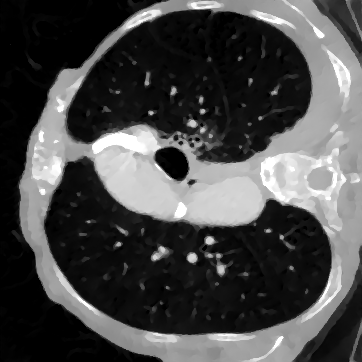

Deep learning-based image reconstruction approaches have demonstrated impressive empirical performance in many imaging modalities. These approaches generally require a large amount of high-quality training data, which is often not available. To circumvent this issue, we develop a novel unsupervised knowledge-transfer paradigm for learned iterative reconstruction within a Bayesian framework. The proposed approach learns an iterative reconstruction network in two phases. The first phase trains a reconstruction network with a set of ordered pairs comprising of ground truth images and measurement data. The second phase fine-tunes the pretrained network to the measurement data without supervision. Furthermore, the framework delivers uncertainty information over the reconstructed image. We present extensive experimental results on low-dose and sparse-view computed tomography, showing that the proposed framework significantly improves reconstruction quality not only visually, but also quantitatively in terms of PSNR and SSIM, and is competitive with several state-of-the-art supervised and unsupervised reconstruction techniques.